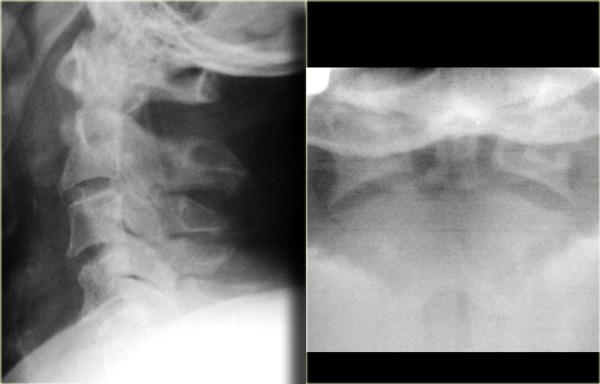

Hình bên trái là một trường hợp gãy mỏm răng loại II khác.

Đôi khi các đường gãy này có thể khó nhận thấy.

Có những hình ảnh giả gãy xương như các đường thấu quang do chồng hình (overprojection) hoặc đường Mach nổi bật (hình minh họa).